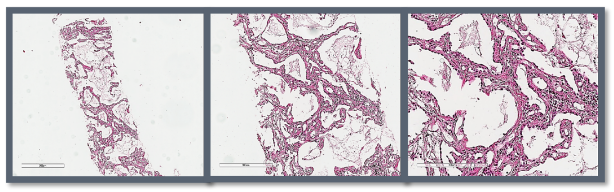

术前活检取出的组织量少。

低功率微波消融后活检取出的组织量明显增多,紧密。

术前活检病理结果为阴性,低功率微波消融后病理结果为阳性。